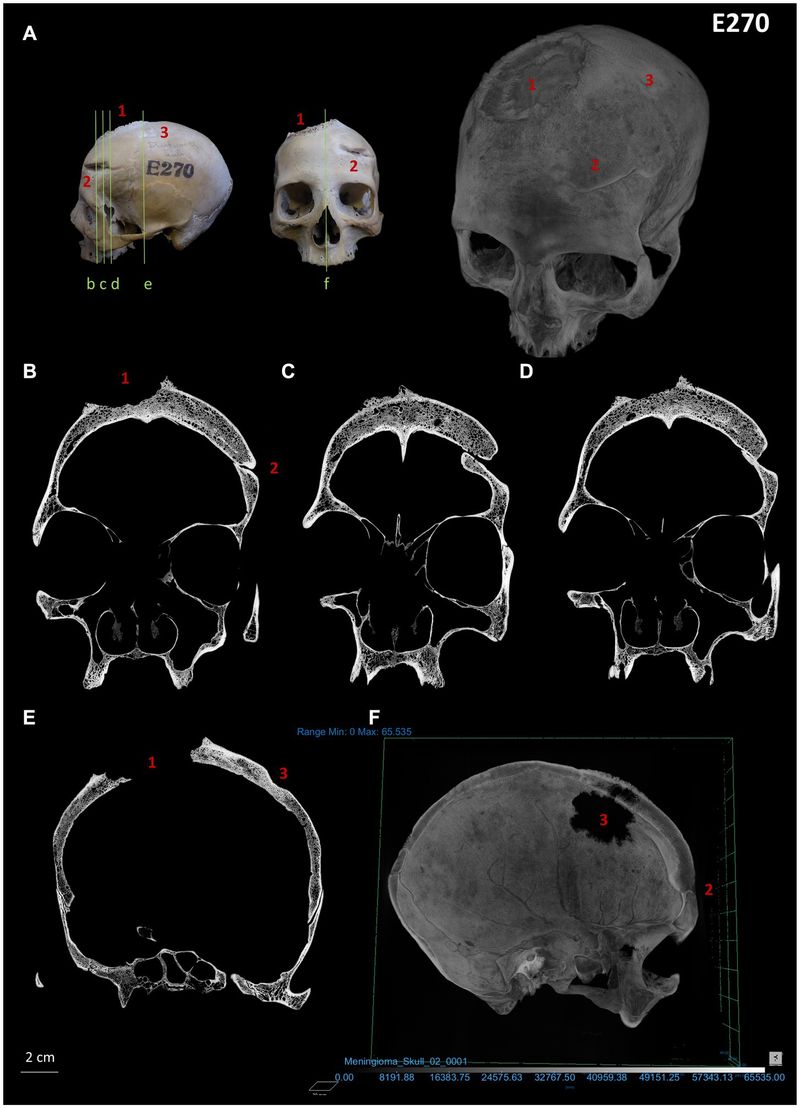

The two skulls, named Skull and Mandible 236, dating from between 2687 and 2345 BCE, belonged to a male individual aged 30 to 35, while Skull E270, dating from between 663 and 343 BCE, belonged to a female individual who was older than 50 years.

Examination of Skull E270 also revealed a significant lesion consistent with a cancerous tumor, resulting in bone destruction. Additionally, two lesions resulting from traumatic injuries were identified, indicating that they had undergone treatment.